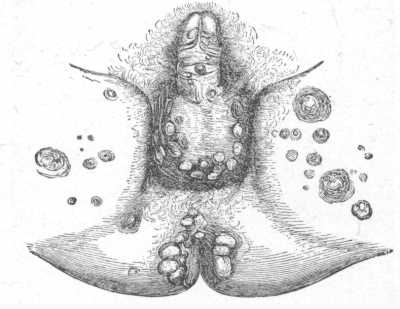

Fig. 13.

Urticaria Pigmentosa.

The nature of the disease is obscure and treatment unsatisfactory. Ordinarily as early youth or adult life is reached it spontaneously disappears. The treatment advised is usually on the same lines as that of chronic urticaria. [Pg 58]